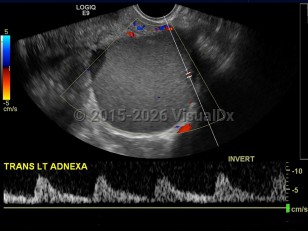

The endometrium is the innermost lining layer of the uterus. Its function is to stabilize and support an early pregnancy. When fragments of endometrial lining are found outside of the uterine cavity, this is referred to as endometriosis.

The exact etiology of this condition is unclear, but the prevailing thoughts are toward retrograde menstruation (endometrial fragments pushed into the abdomen through the fallopian tubes) and localized lymphatic spread. Areas affected can include all abdominal organs but most commonly involve the ovaries, bladder, fallopian tubes, and the uterine support ligaments. Less common sites of involvement may include the umbilicus, incisional scars, and the omentum.

Endometriosis affects approximately 6%-10% of women of reproductive age. Presenting symptoms can be nonspecific and variable but may include fatigue, cyclic pelvic pain, pain with intercourse, abdominal pain, chronic pain, painful periods, or pain with bowel movements or a full bladder. This condition can also be completely asymptomatic and only present as infertility (which affects about one-third of patients) or as an incidental finding at the time of an unrelated surgery. It is sometimes associated with somatic mutations in the ARID1A, PIK3CA, KRAS, or PPP2R1A genes.